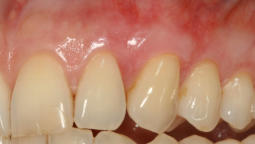

Durch Transplantate kann verlorenes Gewebe wieder aufgebaut werden. Damit wird eine dauerhafte Stabilität der Gewebe und damit auch des Knochens erzielt und eine gute Putzfähigkeit für Zähne oder Implantate erreicht. Beispiele:

Mikrochirurgischer Wundverschluss

Gingivatransplantat fixiert

Zustand 3 Wochen post OP